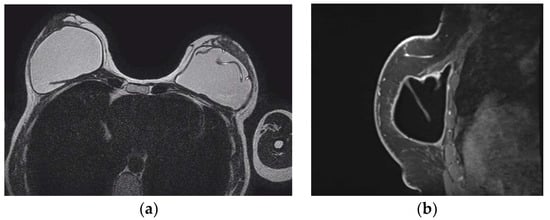

- Wong, T.; Lo, L.W.; Fung, P.Y.; Lai, H.Y.; She, H.L.; Ng, W.K.; Kwok, K.M.; Lee, C.M. Magnetic resonance imaging of breast augmentation: A pictorial review. Insights Imaging 2016, 7, 399–410. [Google Scholar] [CrossRef] [PubMed]

- Norena-Rengifo, B.D.; Sanin-Ramirez, M.P.; Adrada, B.E.; Luengas, A.B.; Martinez de Vega, V.; Guirguis, M.S.; Saldarriaga-Uribe, C. MRI for Evaluation of Complications of Breast Augmentation. Radiographics 2022, 42, 929–946. [Google Scholar] [CrossRef]